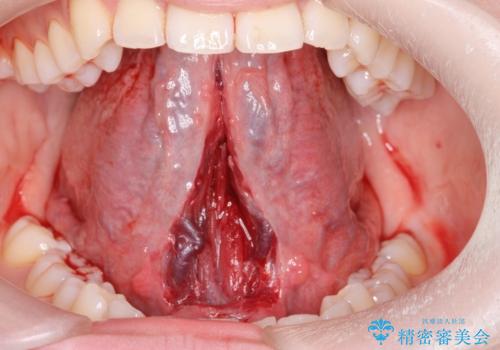

舌小帯切除

- ら行が言いにくいとの事で来院。舌の動きを舌小帯が邪魔していたので舌小帯の形成術を行いました。

舌小帯の形成手術を行うことにより舌が口蓋に届くようになり

ら行が言いやすくなりました。

舌小帯の手術は当日行うことができます。

- 外科手術のため、術後に出血、痛みや腫れ、違和感を伴います